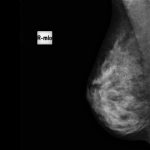

検査1マンモグラフィ検査

マンモグラフィ検査はX腺を使用し、腫瘤や石灰化の有無を調べる検査です。

特にカルシウム成分の沈着による石灰化の検出に有効であり、例えばカテゴリー3の石灰化が乳がんである可能性は概ね5-10%と言われています。石灰化病変の検出においては、超音波検査やMRI検査に優ります。

- マンモグラフィ検査は、”腫瘤(しこり)”と”石灰化(石灰化の沈着)”という所見で発見される乳がんのいずれの病変も確認可能です。